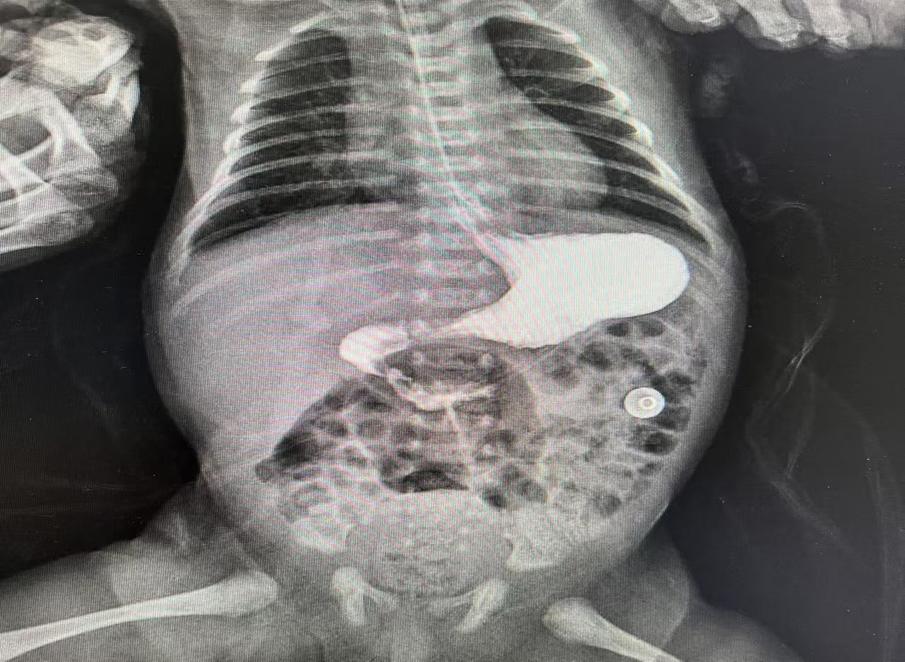

術(shù)前造影提示十二指腸遠(yuǎn)端閉鎖

分娩將至,陳女士來到衡陽市中心醫(yī)院待產(chǎn)。醫(yī)院高度重視,組織多學(xué)科聯(lián)合會診,確定分娩方式,嚴(yán)密觀察產(chǎn)婦情況。1月11日下午,陳女士足月剖產(chǎn)一名3.44KG的男嬰,出生后頻繁嘔吐,隨即轉(zhuǎn)入新生兒科進(jìn)行監(jiān)護(hù)。主管醫(yī)生許承輝立即給患兒下胃管進(jìn)行胃腸減壓、全靜脈營養(yǎng),同時(shí)進(jìn)行上消化道造影檢查,進(jìn)一步明確了患兒十二指腸閉鎖的診斷。隨即新生兒科主任雷明、副主任王紅燕立即組織MDT聯(lián)合診治,制定最佳手術(shù)方案,充分術(shù)前評估,完善術(shù)前準(zhǔn)備。